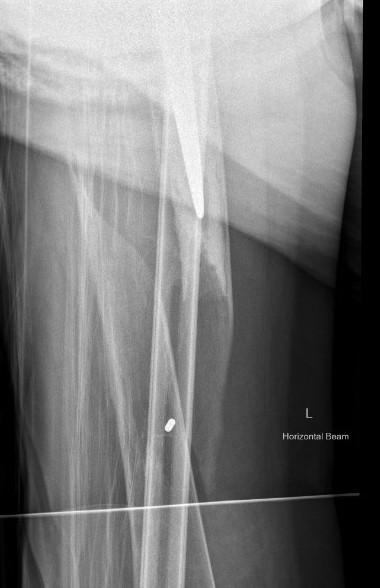

Type C: Fracture distal to tip of stem

Management

ORIF Locking cable plate +/- cortical strut allograft

- overlap femoral implant

- to distal femur